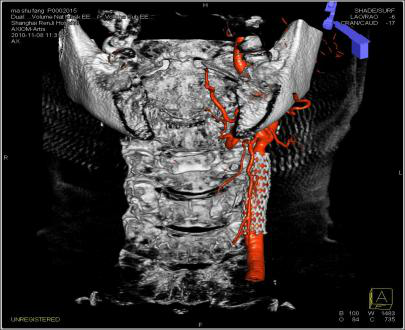

3. 颌面部肿瘤

颌面部血管瘤栓塞术,额面部血管瘤具有复杂迂曲的血供,DynaCT增强扫描帮助鉴别滋养血管,功能学影像Dyna PBV Neuro为瘤体栓塞终点做精准评估。